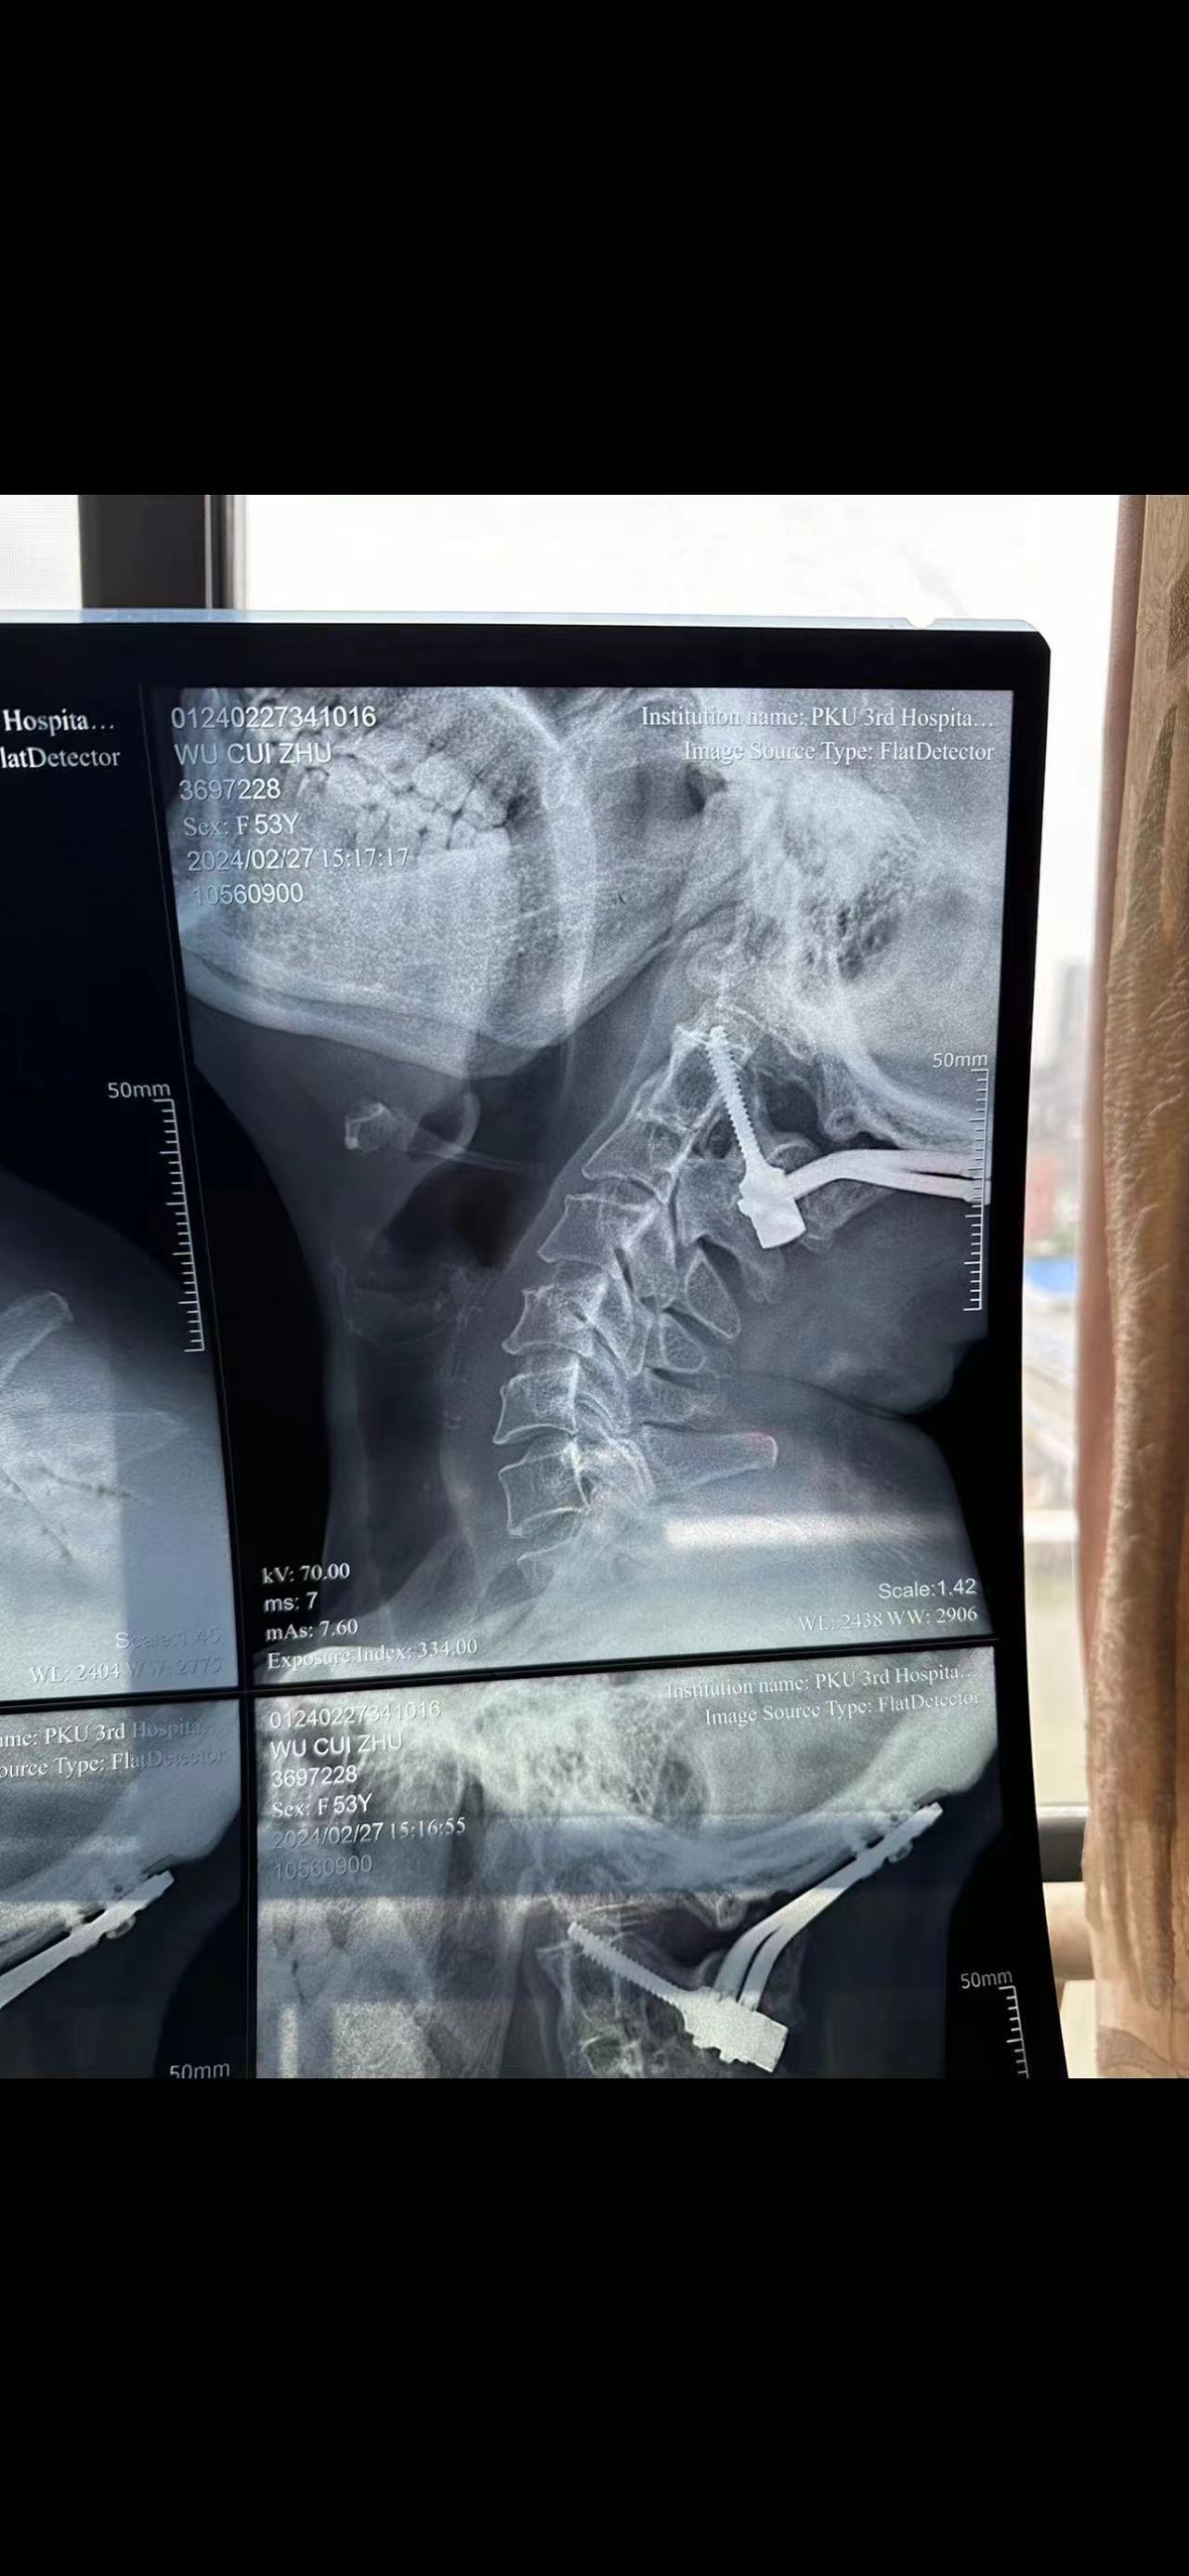

手术#

• 日期:2023.09

• 医院:北三医院

• 主刀:王超

• 术后影像:

• 2024.02.27,复查,对位良好,偶尔会肩甲骨酸,坐下就不酸。